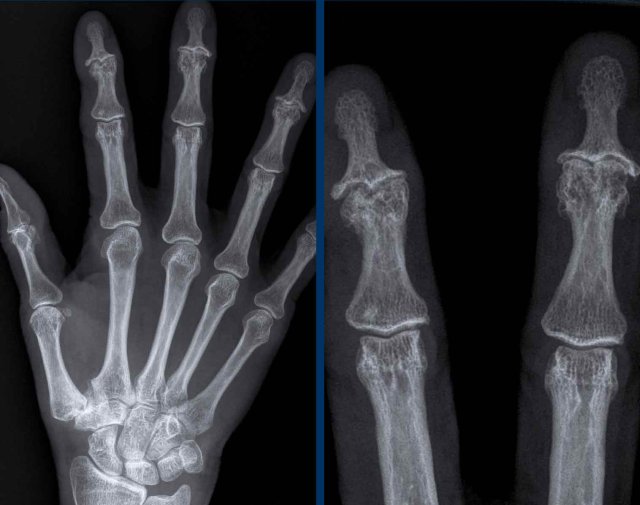

Sausage digits and pencil in cup deformity in Psoriatic arthritis Sausage digits and pencil in cup deformity in Psoriatic arthritis

Sausage digits

Typical appearance of dactylitis “sausage digits” with soft tissue swelling and pencil-in-cup deformity of DIP 1-2 and 5 of the left hand in a patient with psoriatc arthritis.

Notice that the MCP joints are not involved (unlike in RA).